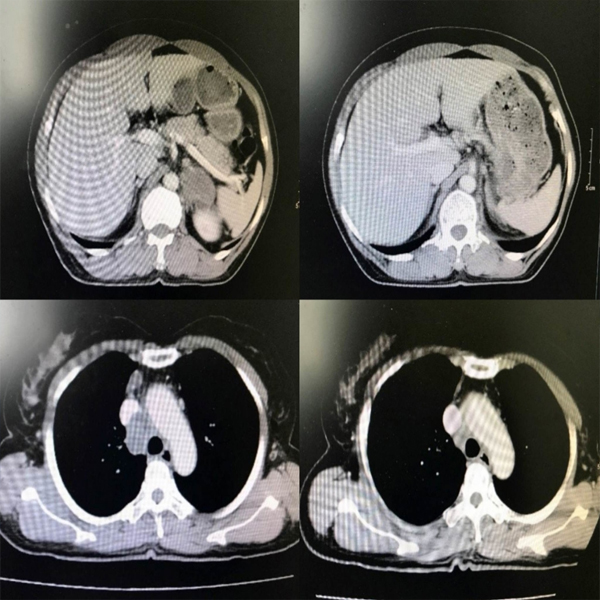

10/07/2023VNEXPRESS.NET: Bằng liệu pháp miễn dịch, người phụ nữ 57 tuổi, mắc ung thư phổi giai đoạn cuối đã lui bệnh chỉ sau ba chu kỳ điều trị, các khối u tiêu biến.

Theo bác sĩ Phạm Tuấn Anh, Phó trưởng khoa Điều trị theo yêu cầu, Bệnh viện K Trung ương, đây là một trong những trường hợp được cứu sống ngoạn mục tại viện.